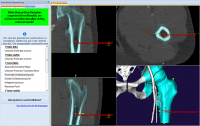

Phần mềm MediCAD dự đoán chính xác kích thước trên 90%, giảm rủi ro cho bệnh nhân và giảm chi phí nhiều trong quá trình phẫu thuật, điều trị các bệnh về xương, khớp háng, hông, đùi.

Giao diện của Phần mềm MediCAD dễ hiểu, rõ ràng, dễ thao tác. Các bác sĩ có thể tập trung, phóng to các bộ phận quan trọng trong việc lên kế hoạch điều trị bệnh.